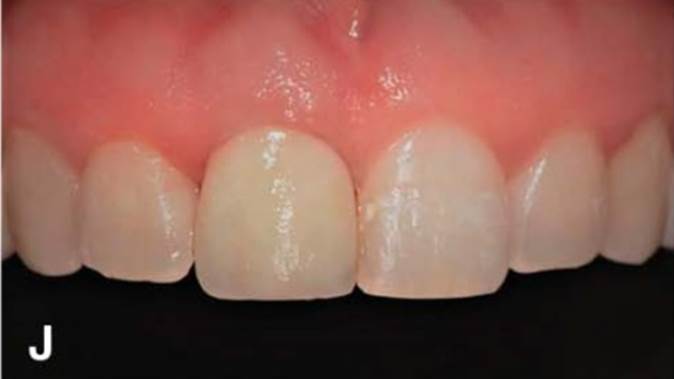

“Immediate loading of single AnyRidge implants

is a highly successful treatment modality. ”

Clinical case: Immediate post-extraction insertion of implant & immediate loading

- Courtesy of Prof. Giuseppe Luongo, Italy -

Keywords

AnyRidge, immediate loading, single implant, multicenter study, maxillary anterior, Prof. Giuseppe Luongo, single replacement

Products:

AnyRidge implant system

Reference

Immediate functional loading of single implants: a multicenter study with 4 years of follow-up

/J Dent Res Dent Clin Dent Prospect 2018; 12(1):26-37 | doi: 10.15171/joddd.2018.005

https://www.ncbi.nlm.nih.gov/pubmed/29732018